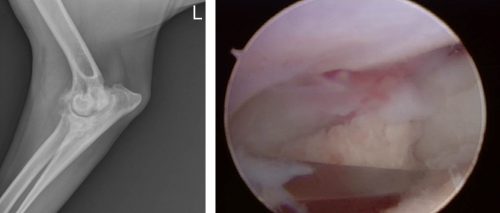

Is your dog experiencing front leg lameness? By Rebecca Wolf, VMD, DACVS-SA Many of the orthopedic problems we diagnose in forelimbs are now treated arthroscopically, meaning smaller incisions, fewer complications, and less postoperative pain. In the shoulder, osteochondrosis dissecans (OCD)…